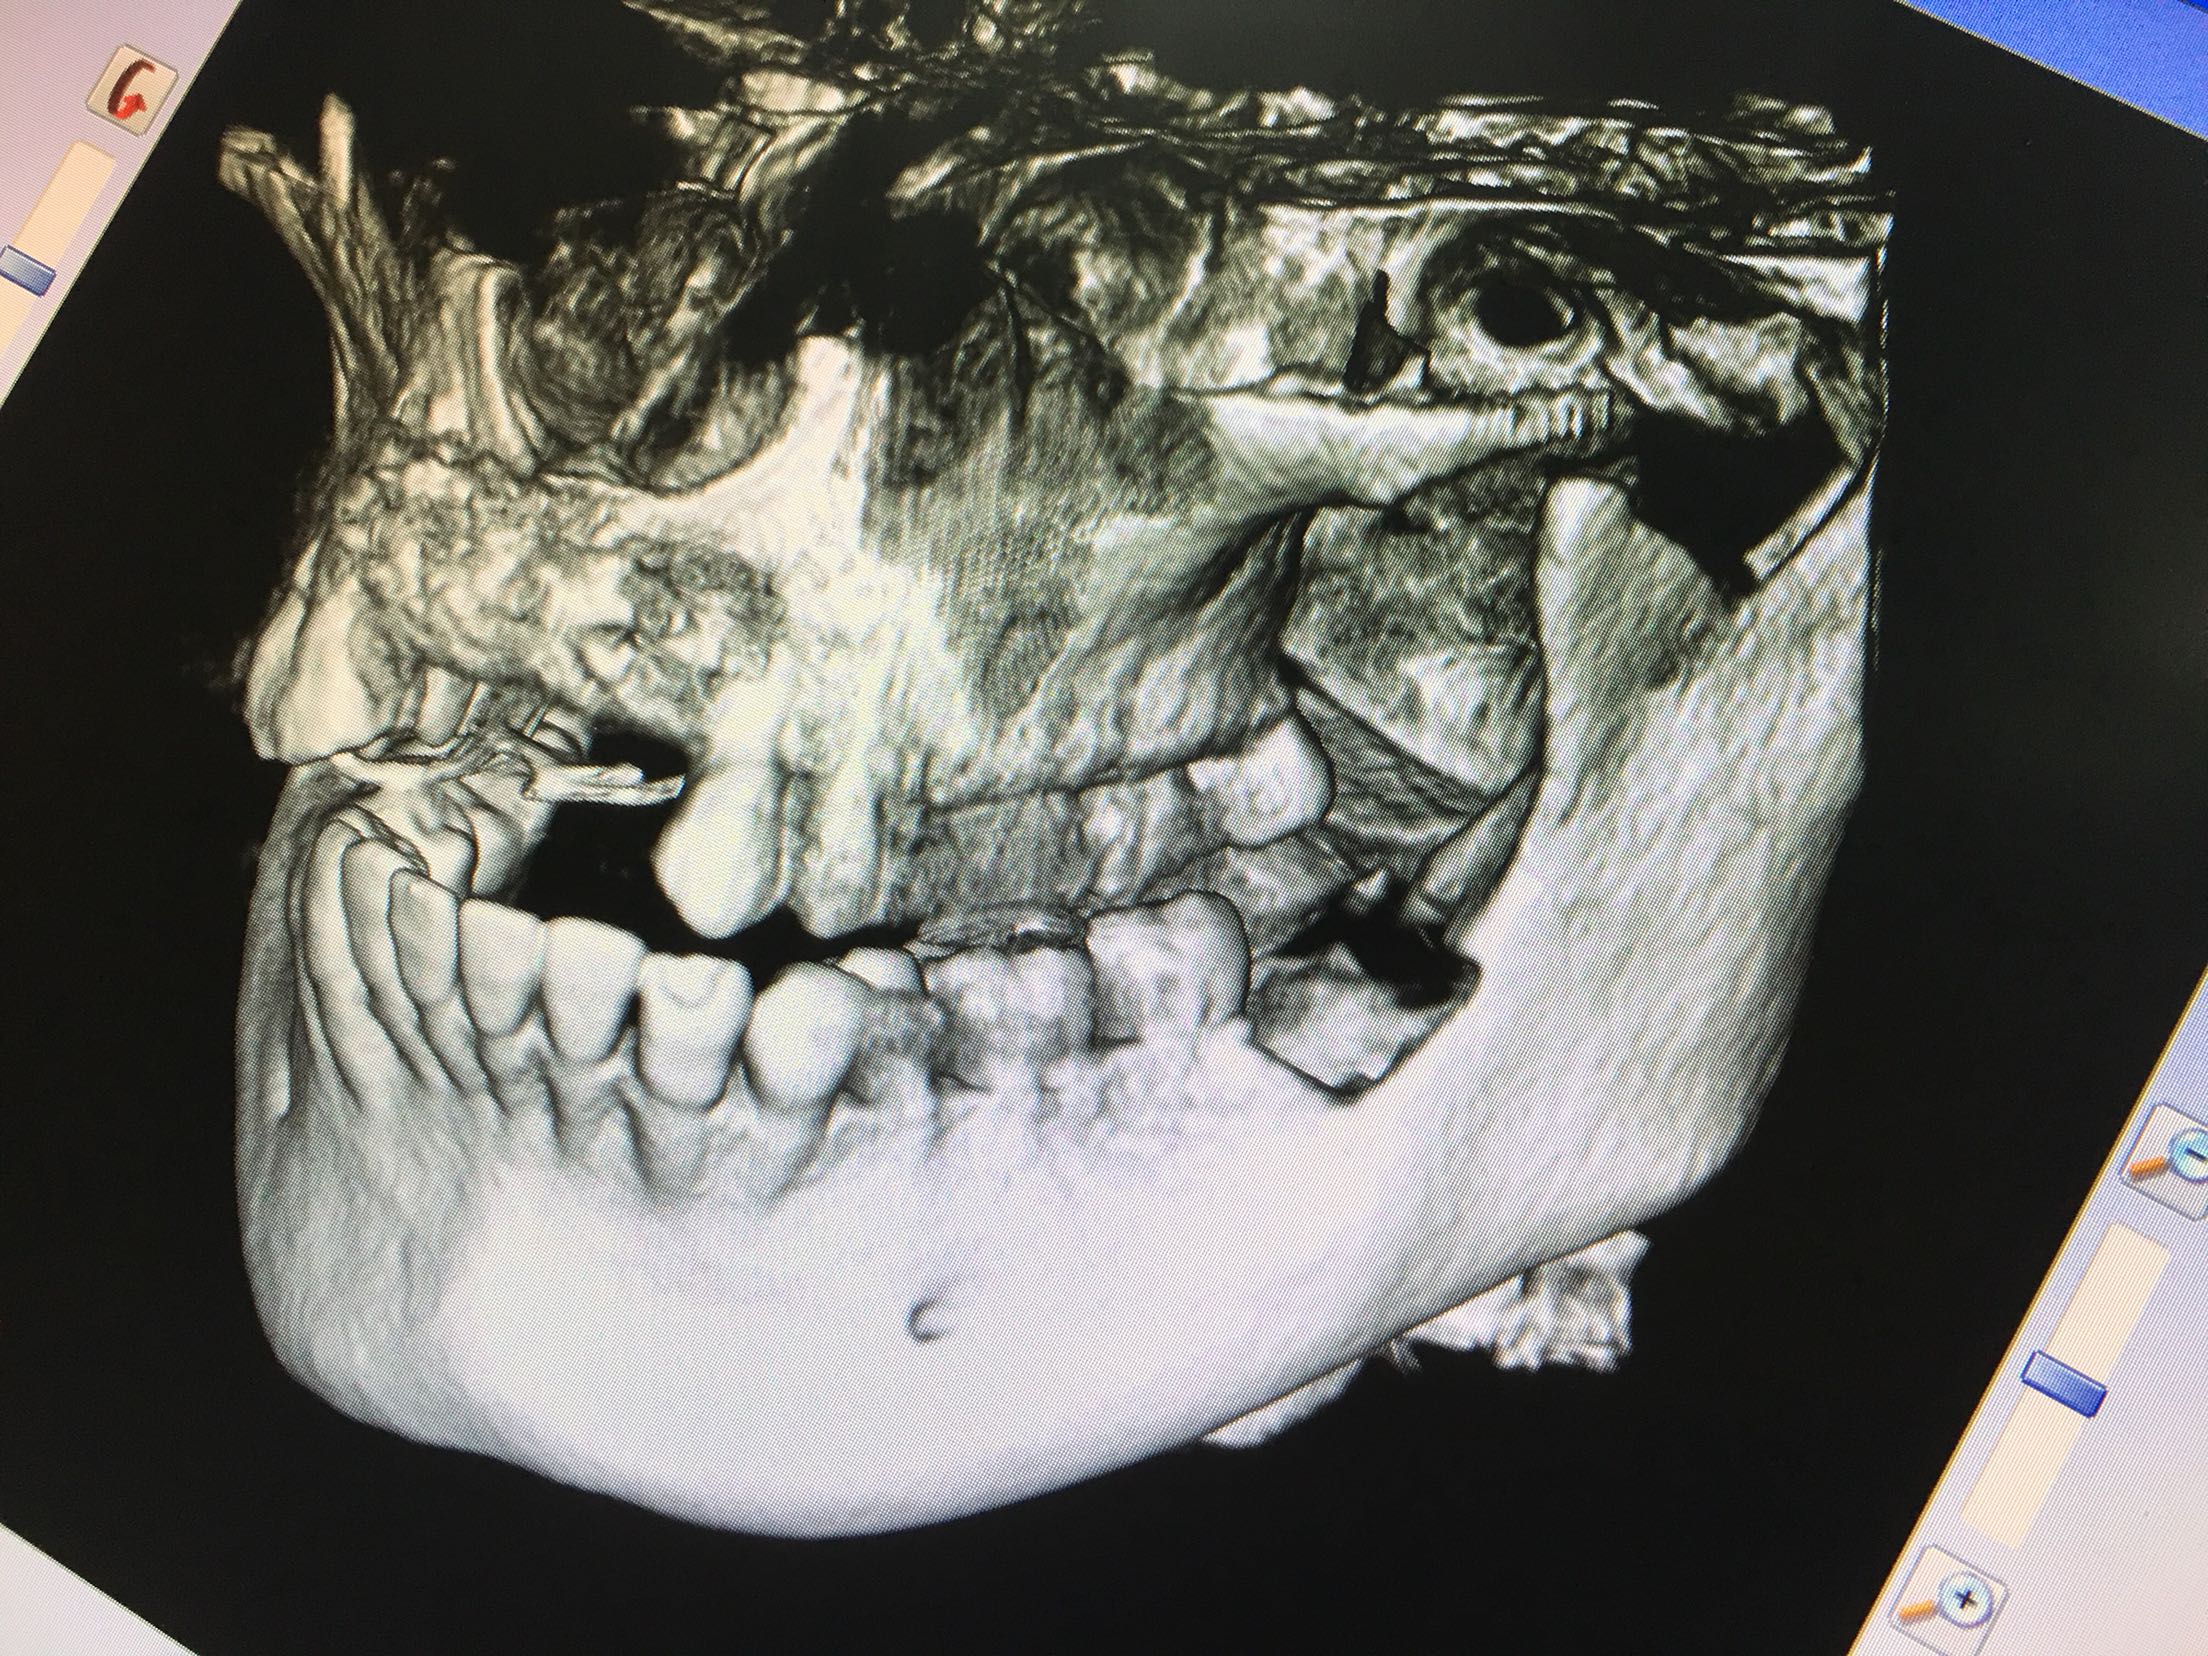

CBCT示11、12、21、22牙缺失,牙槽骨呈刀刃状,38、48牙阻生。

38、48牙超刀拔除,取双侧骨块,11、12、21、22梯形切口切开、翻瓣,切断粘骨膜松弛,骨块钛钉固定唇侧,植入Bio-ss骨粉0.5g,覆盖生物膜,严密缝合!嘱半年后种植!